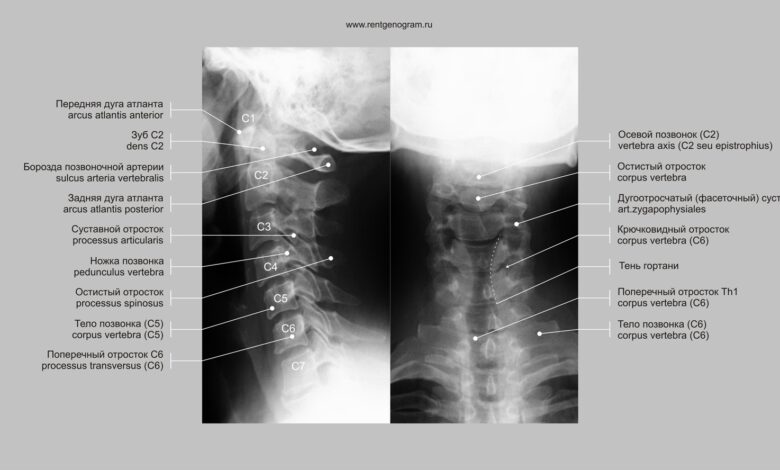

Рентген позвоночника в профиле

Проведение рентгенографии позвоночника в профиль является важным этапом в диагностике различных заболеваний позвоночника, таких как сколиоз, остеохондроз, травмы и др.

Исследование позволяет получить детальное изображение структуры позвоночного столба в боковой проекции, что обеспечивает возможность выявления патологий, незаметных на обычных снимках.

Рентген позвоночника в профиль помогает определить степень кривизны позвоночника, выявить деформации и изменения в структуре позвонков.